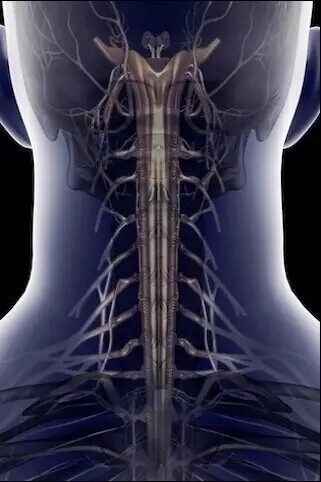

颈部脊柱、神经

头颅、颈椎

颈椎、大脑